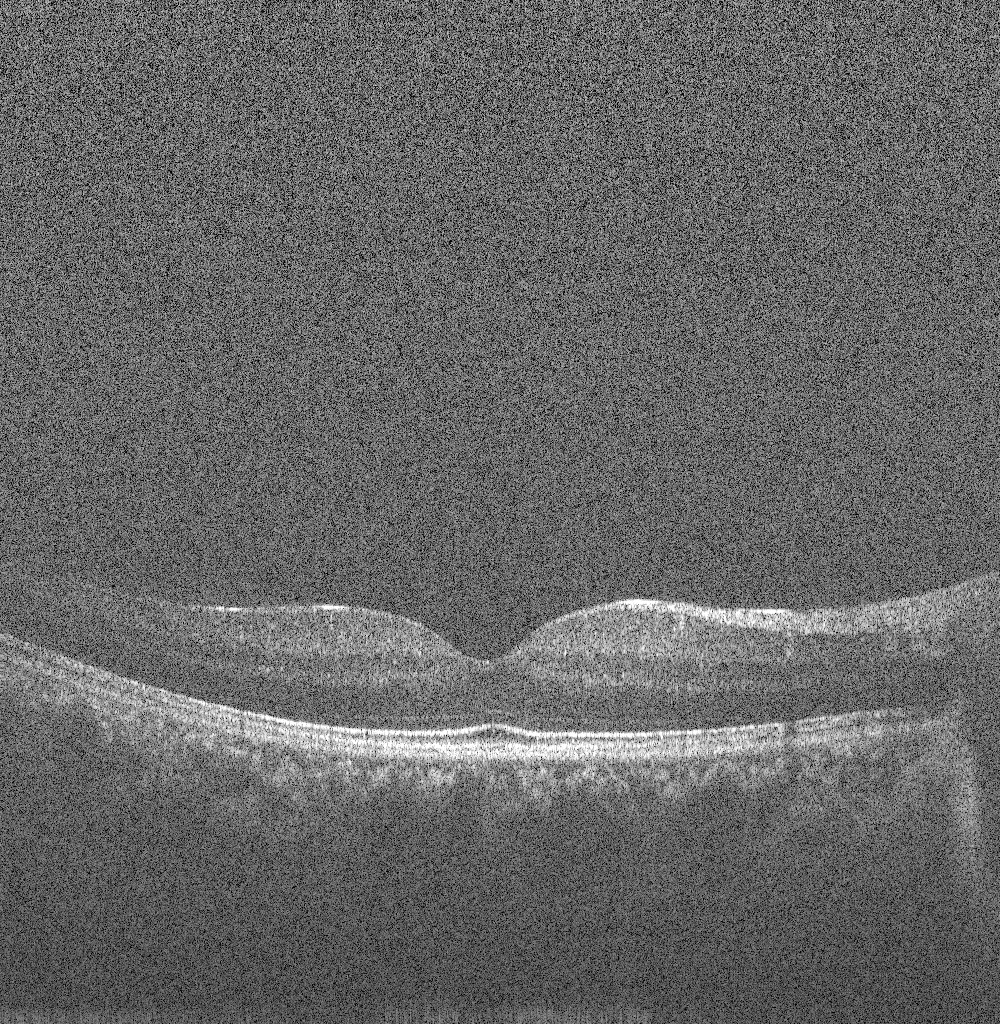

Speckle is a fundamental property of the signals and images acquired by narrow-band detection systems like SAR, ultrasound and OCT. In OCT, not only the optical properties of the system, but also the motion of the subject to be imaged, size and temporal coherence of the light source, multiple scattering, phase deviation of the beam and aperture of the detector can affect the speckle [9]. Two main processes affect the spatial coherence of the returning light beam which is used for image reconstruction: 1) multiple back-scattering of the beam, and 2) random delays for the forward-propagating and returning beam caused by multiple forward scattering. In the case of tissue imaging, since the tissue is packed with sub-wavelength diameter particles which act as scatterers, both of these phenomena contribute to the creation of speckle. As stated in [9], two types of speckle are present in OCT images: signal-carrying speckle which originates from the sample volume in the focal zone; and signal-degrading speckle which is created by multiple-scattered out-of-focus light. The latter kind is what that is considered as speckle noise. Fig. 3 displays the common scene in retinal OCT imaging: a highly noisy image.

Refer to caption

Figure 3: Typical retinal OCT image degraded by speckle noise